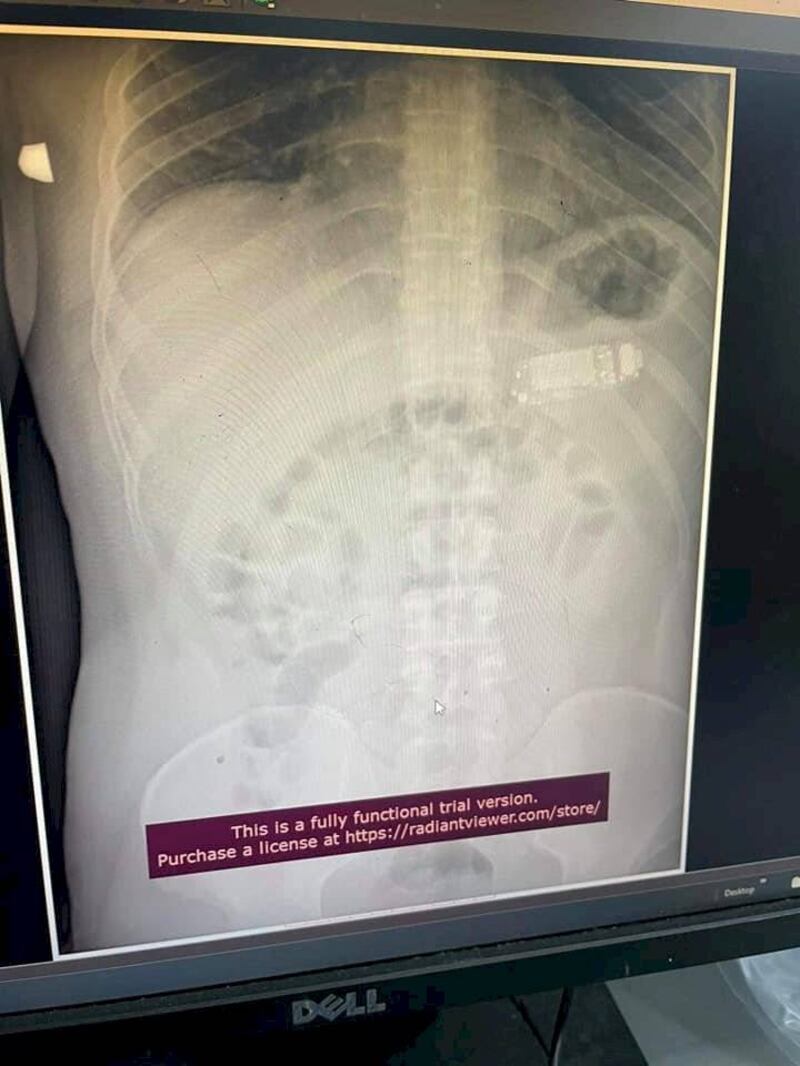

Tras este hecho insólito, el doctor Skender Teljaku, cirujano jefe, publicó la radiografía y el procedimiento en su Facebook.

De acuerdo a lo señalado por el diario Metro, la cirugía se realizó sin ningún problema y no hubo necesidad de abrir la zona abdominal. El celular se separó en tres partes y se logró extraer con una endoscopia sin necesidad de abrir el estómago.